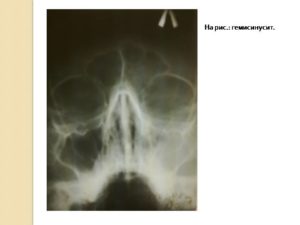

Заключение делается на основе рентгеновского снимка.

Постановка диагноза не вызывает совершенно никаких сложностей, так как симптомы болезни довольно ярко выражены. Для подтверждения диагноза проводится рентгенологическое исследование пазух носа, а также в некоторых случаях проводится томография.